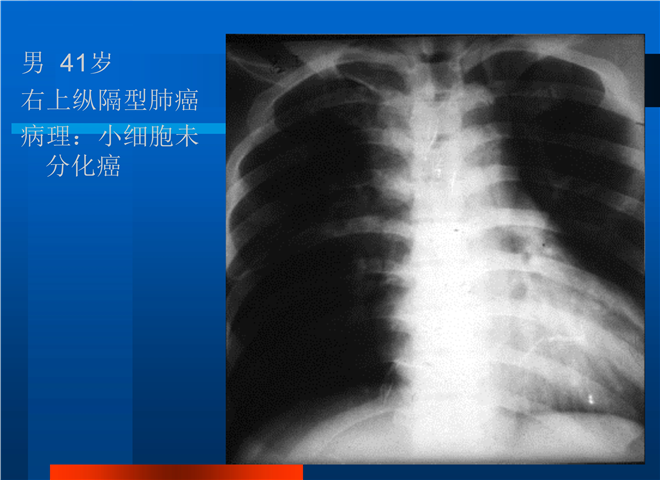

04_肺癌的介入治疗